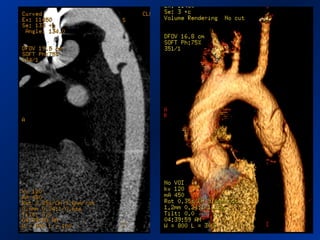

• Preoperative CT 1mm imaging to include pelvisPreoperative CT 1mm imaging to include pelvis